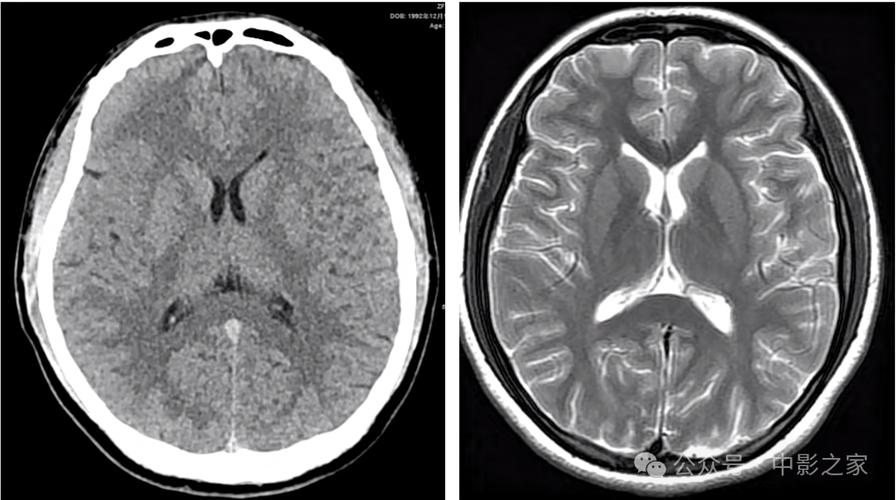

-

磁共振成像,特别是DWI序列(弥散加权成像)

- 这是目前诊断早期脑梗死的“金标准”,DWI对水分子的微观运动极其敏感,能在发病后30分钟到2小时内就发现缺血坏死的脑组织,表现为明显的高信号(亮点),而且边界清晰。

- 如果您或您的家人被怀疑脑梗死,但CT正常,医生一定会建议尽快做MRI检查。

CT血管造影

- 这是在CT基础上进行的增强扫描,可以清晰地显示颅内大血管(如颈内动脉、大脑中动脉等)有没有堵塞、狭窄或夹层,它能帮助医生找到病因,并评估是否适合进行溶栓或取栓治疗。